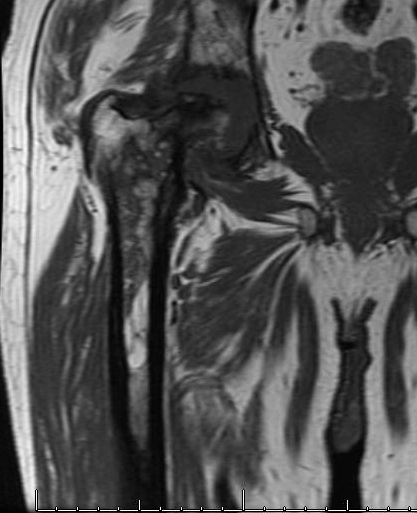

MRI

Increased signal on TI

Abscess

- high signal rim with low signal in middle

- rim / ring enhancement with gadolinium